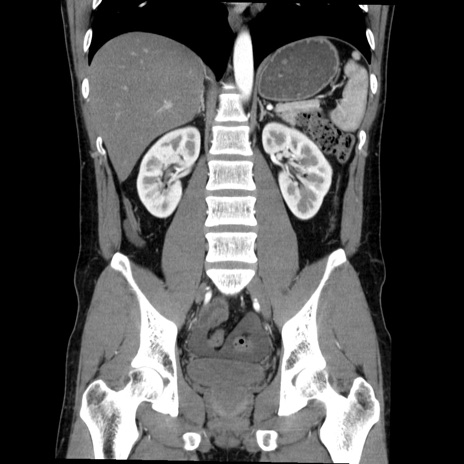

症例36(冠状断像)

【症例】20歳代 男性

【主訴】心窩部痛

【現病歴】今朝より上腹部痛あり。一旦軽快していたが再度出現したため救急要請。昨日夕に白身の魚を含む刺身を食べた。

【身体所見】BP 136/89mmHg、HR 74/min、BT 37.0℃、腹部:膨満、軟、心窩部に圧痛あり。反跳痛なし、筋性防御なし、腸雑音やや亢進あり。

【データ】WBC 17700、CRP 0.48